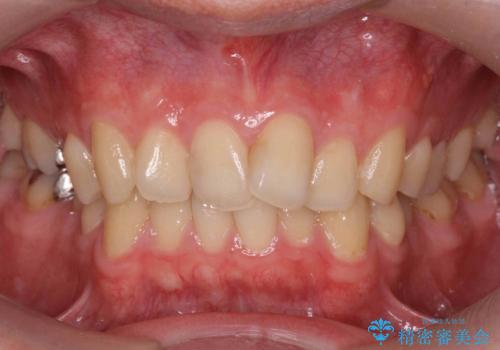

[ 前歯のねじれ・がたつき ] マウスピース矯正

![[ 前歯のねじれ・がたつき ] マウスピース矯正の症例 治療前](https://seimitsushinbi.jp/wp/wp-content/uploads/2024/02/4007c6479f6bce11863dcdd32ed5e39b-500x350.jpg?v=1708502552)

![[ 前歯のねじれ・がたつき ] マウスピース矯正の症例 治療後](https://seimitsushinbi.jp/wp/wp-content/uploads/2024/02/e7a01485e4f4dd0da04705fde4cc34cc-500x350.jpg?v=1708502585)